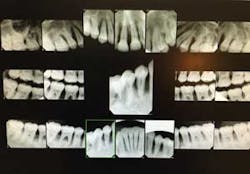

A 17-year-old, African American female, well nourished and otherwise healthy, was referred for bone loss associated with teeth Nos. 21, 22, 23, 24, 25, 27, and 28 (figures 1 and 2).

The patient underwent full-mouth periodontal and radiographic examination. A blood chemistry profile and complete blood count was advised and obtained to eliminate any systemic abnormalities.

A panoramic radiograph (figure 8) and cone beam CT (CBCT) scan were obtained for evaluation of alveolar bone height and width and all sinus and mental foramen positions.